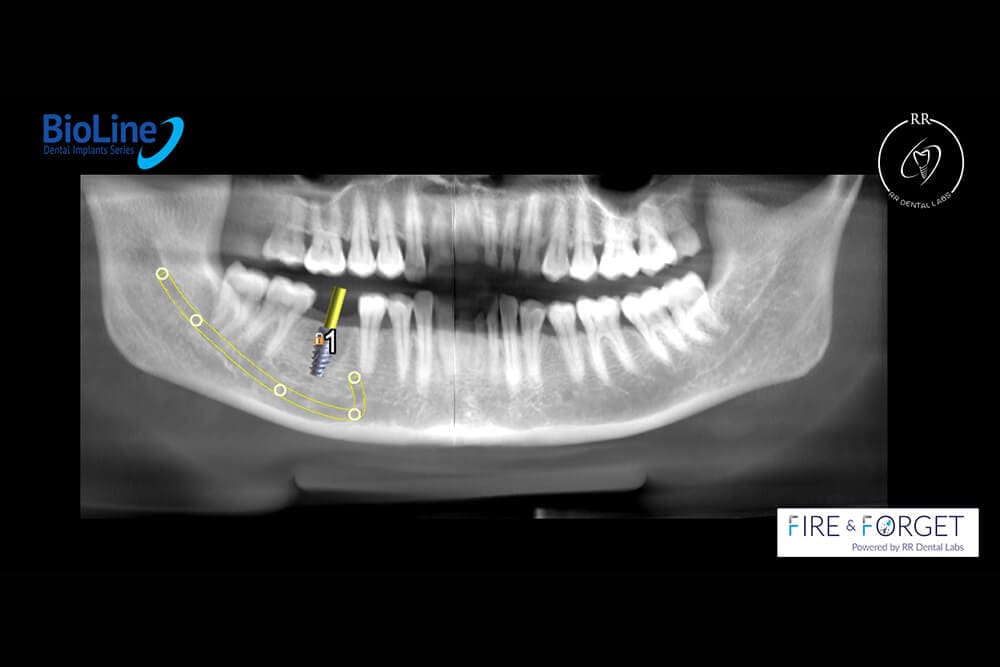

Case 26